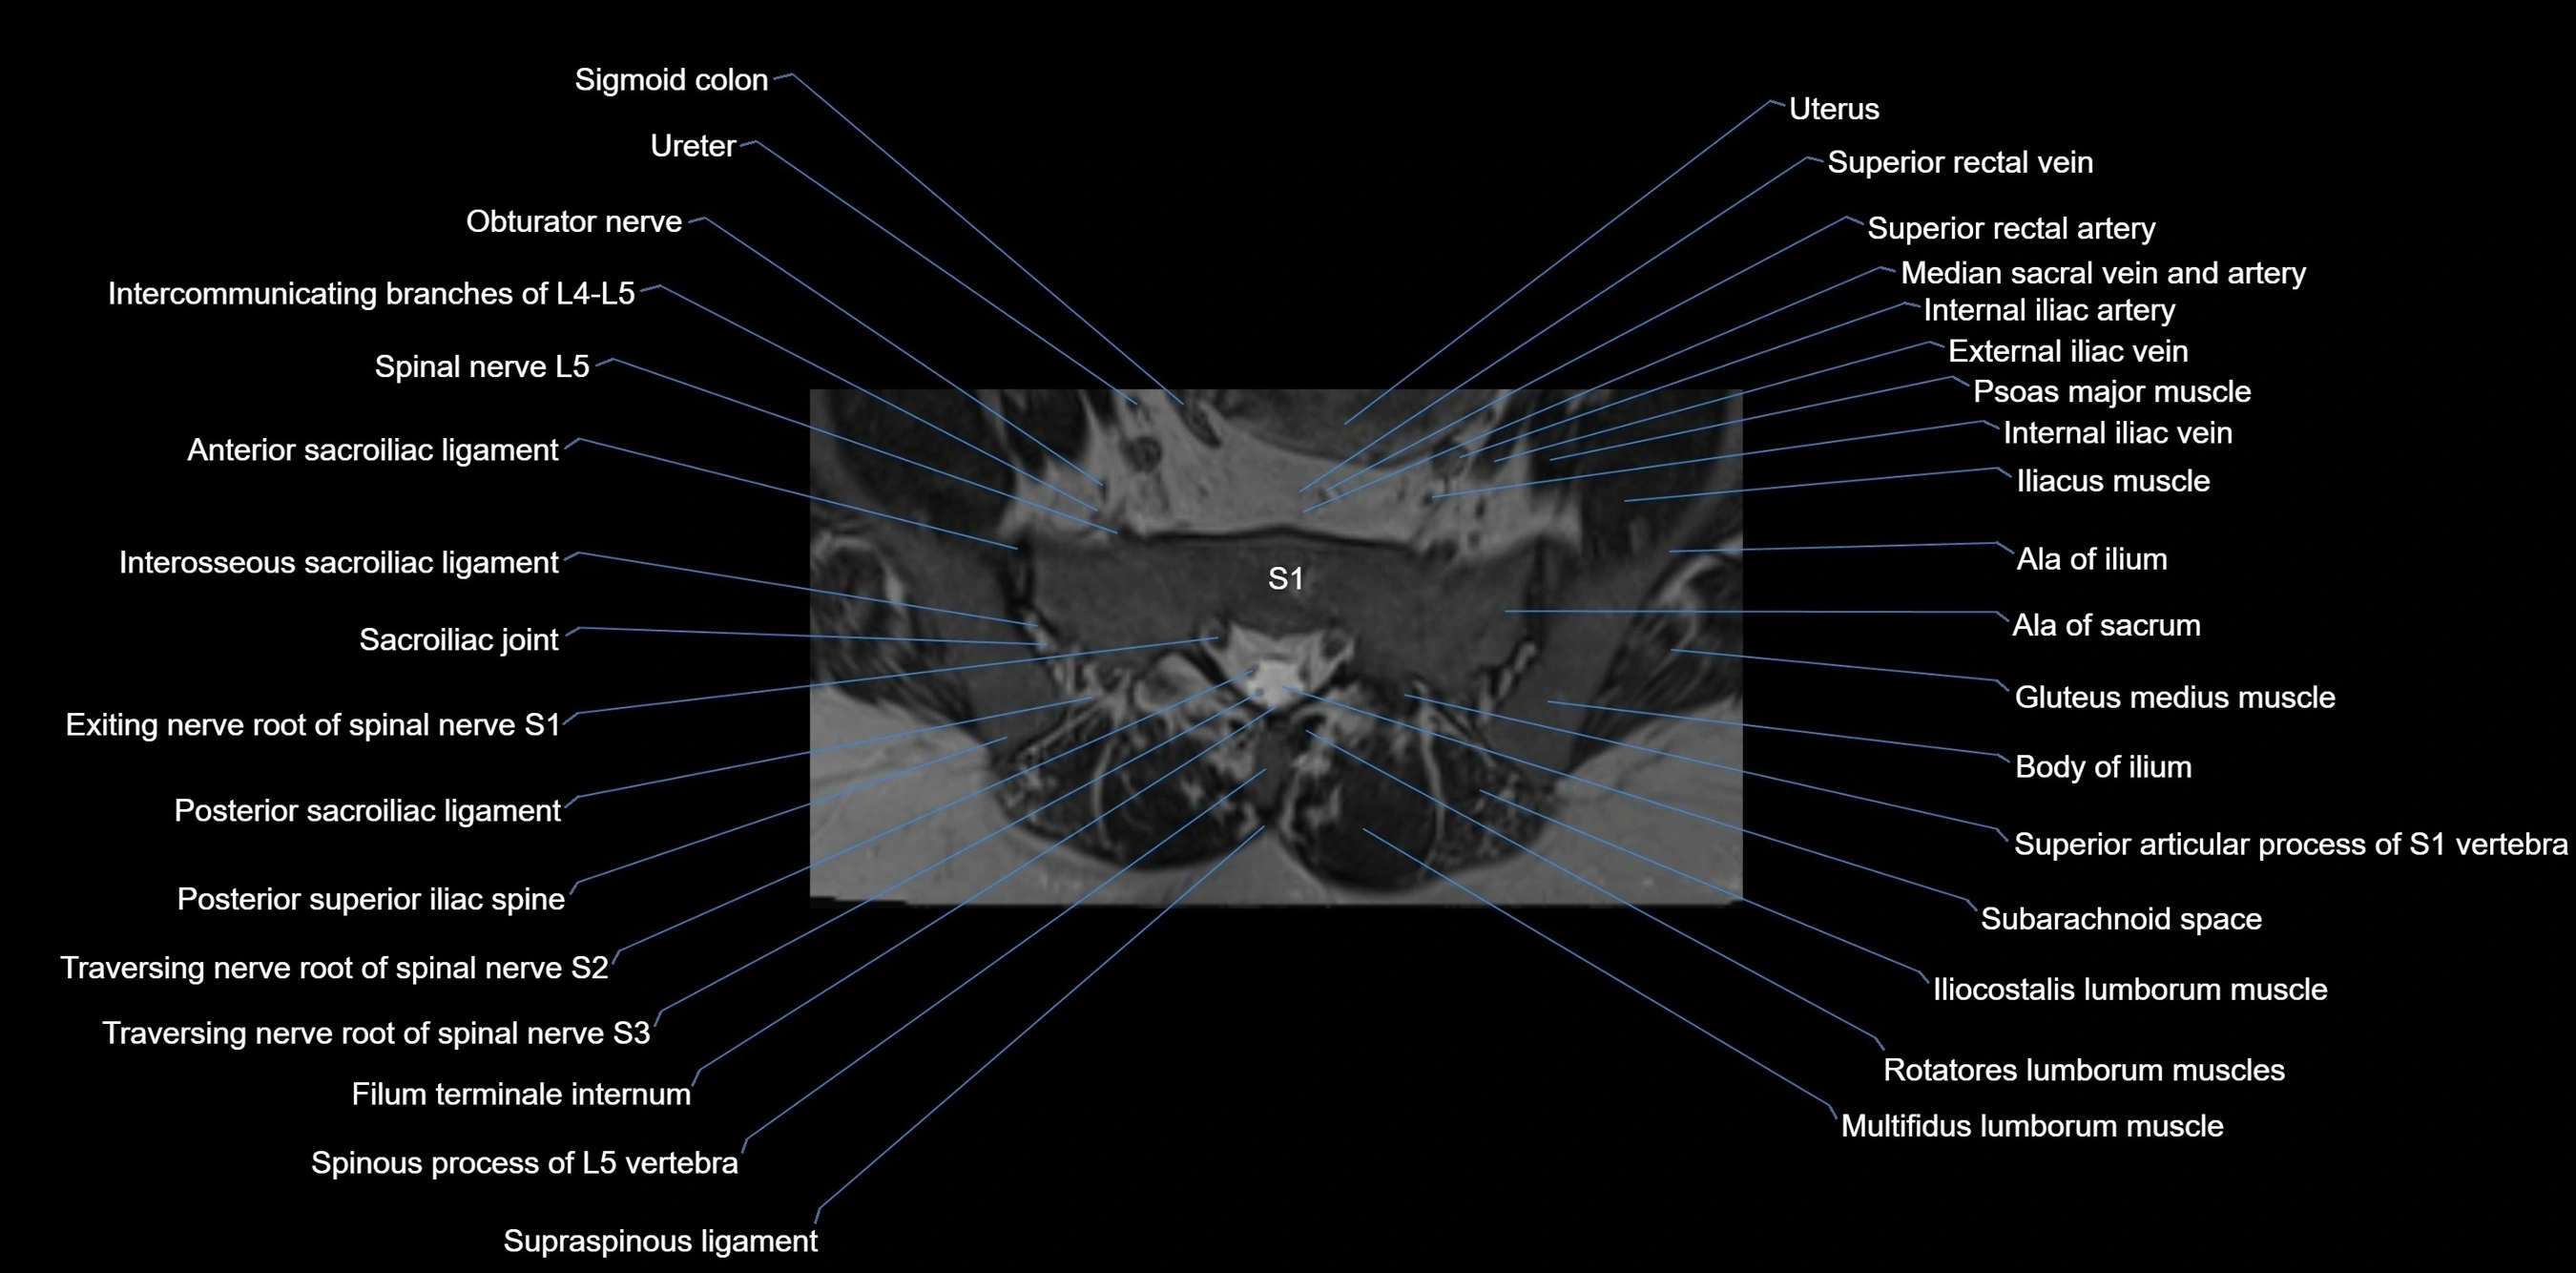

MRI image

image